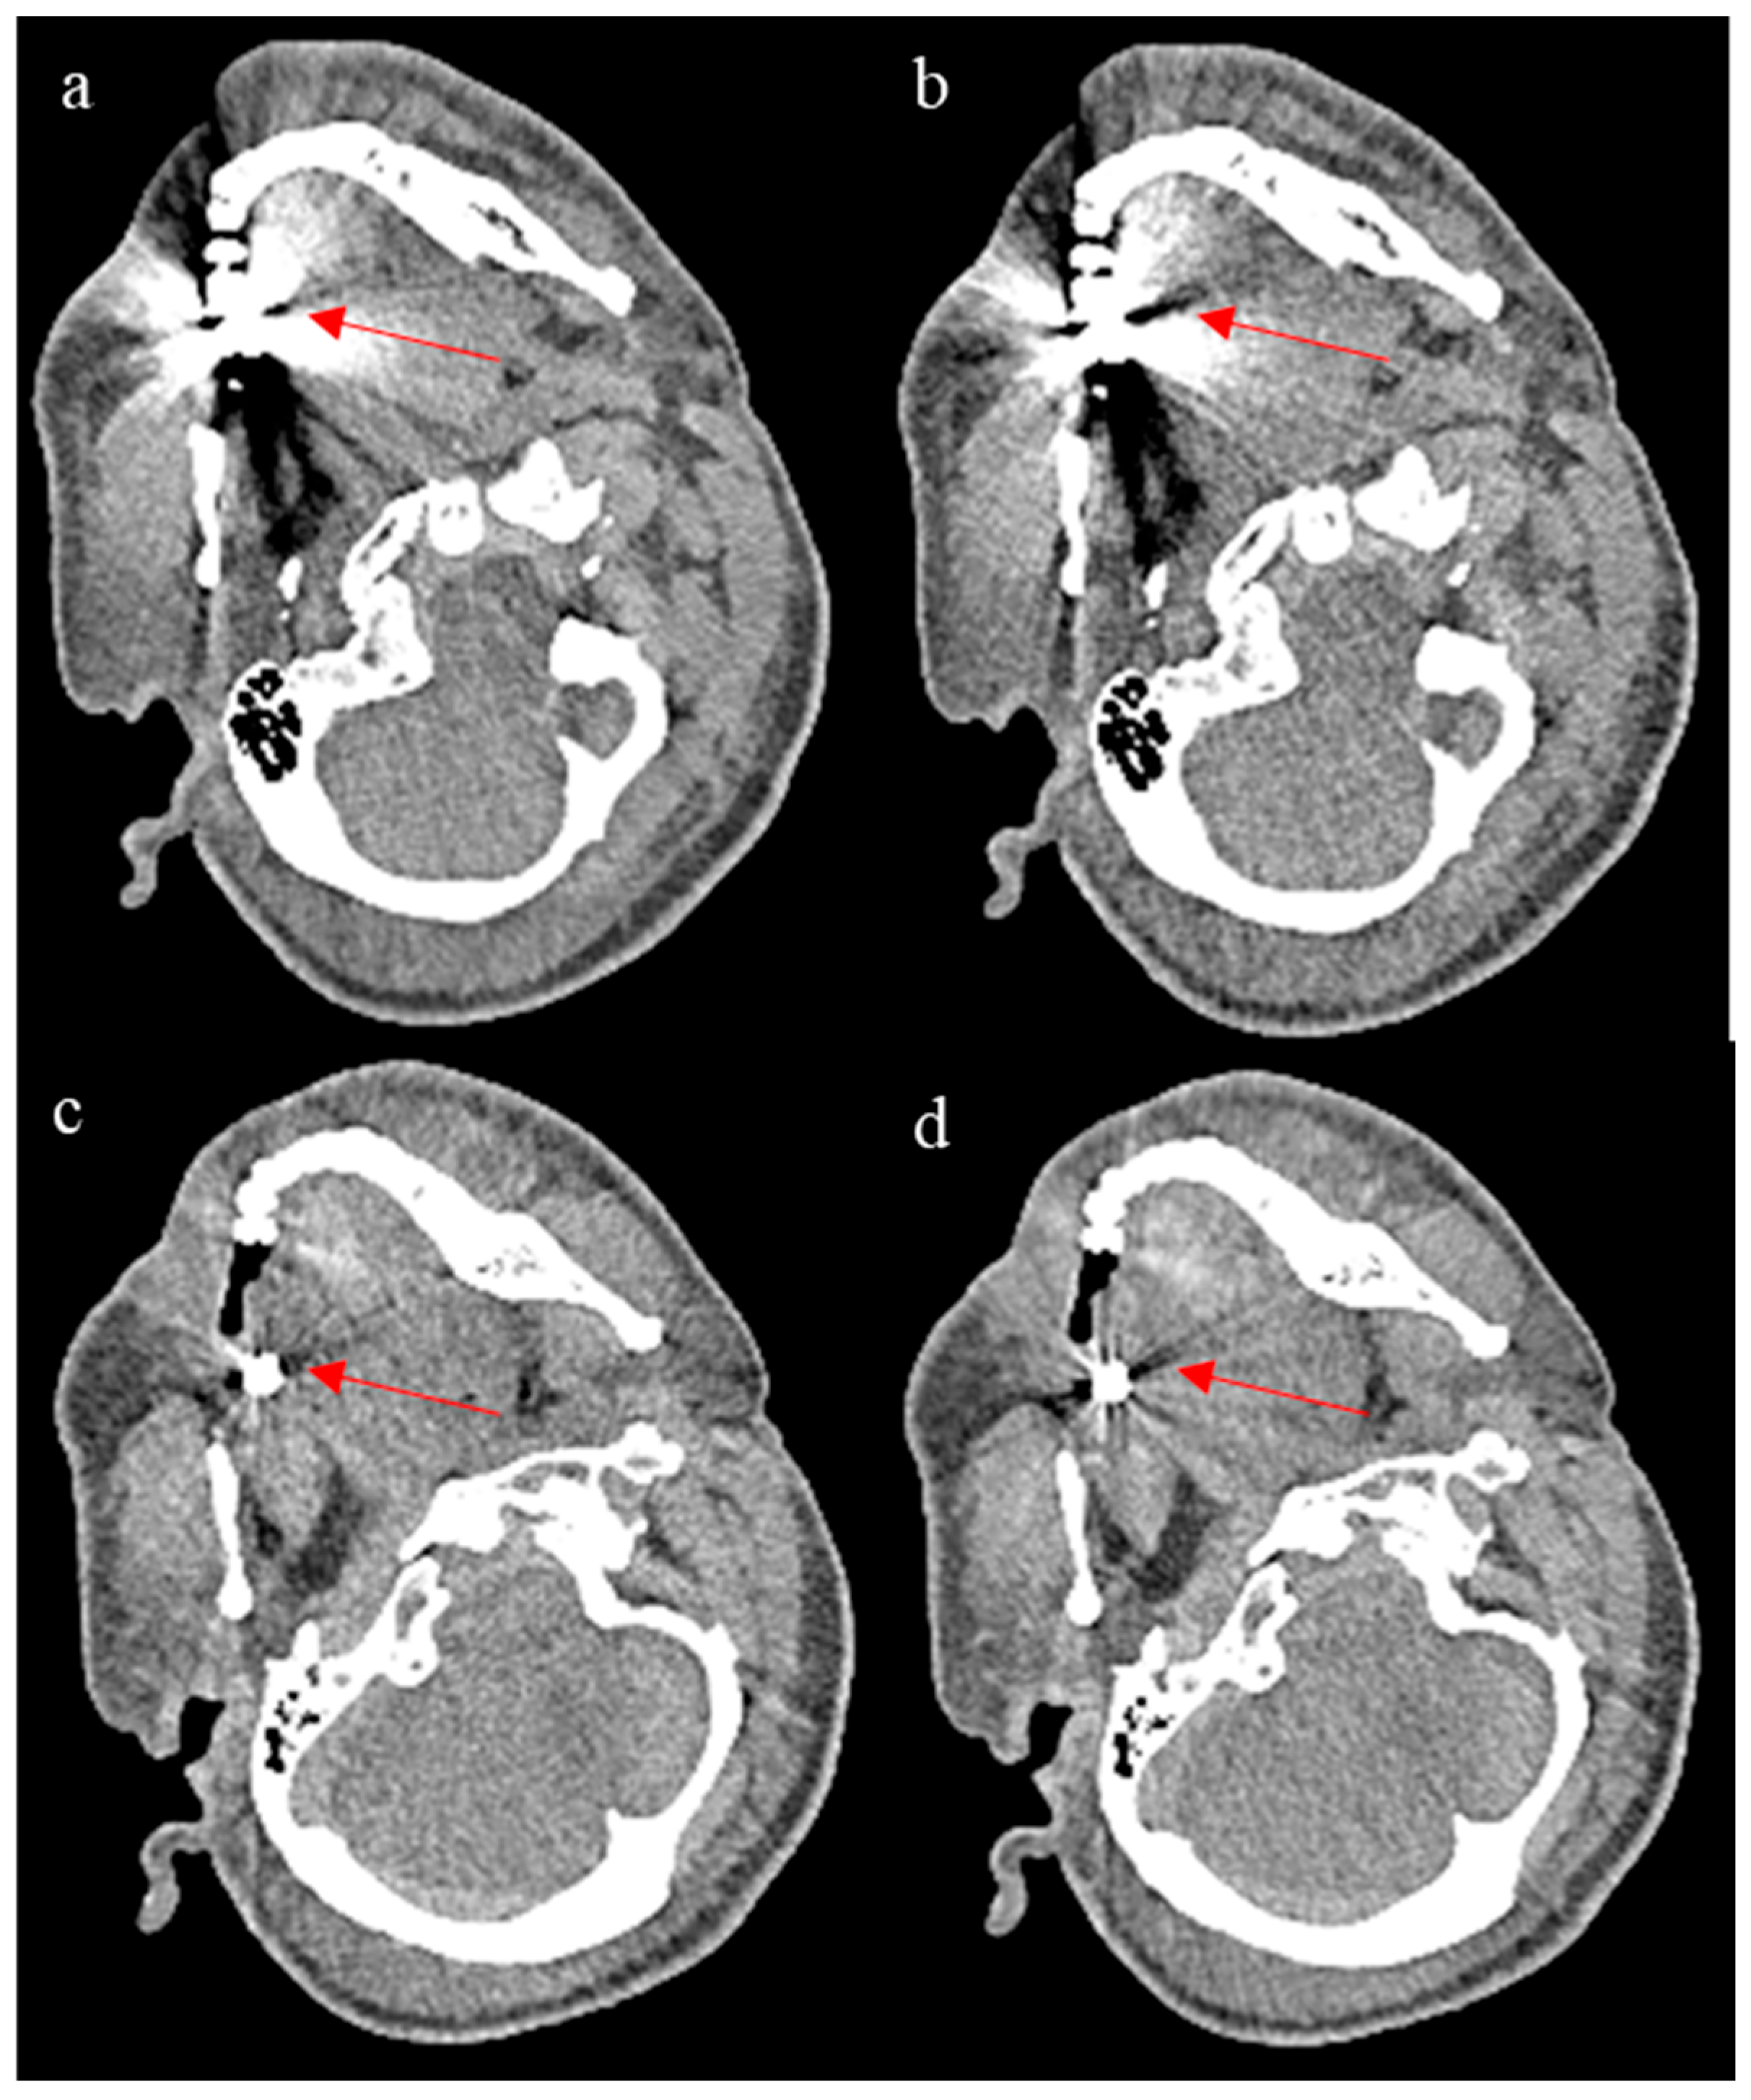

3.2. ROI Results

| Organ | Mean HU | SD | Difference HU (%) |

|---|---|---|---|

| Vitreous LQ | 18.75 | 17.60 | 7.95 |

| Vitreous ErisNet | 18.00 | 16.20 | |

| Brain LQ | 45.50 | 18.85 | 18.30 |

| Brain ErisNet | 46.00 | 15.40 | |

| Liver LQ | 59.00 | 19.65 | 13.36 |

| Liver ErisNet | 58.00 | 17.03 | |

| Spleen LQ | 54.61 | 25.11 | 12.01 |

| Spleen ErisNet | 52.34 | 22.09 | |

| Muscle LQ | 52.12 | 25.65 | 9.35 |

| Muscle ErisNet | 50.74 | 23.26 |